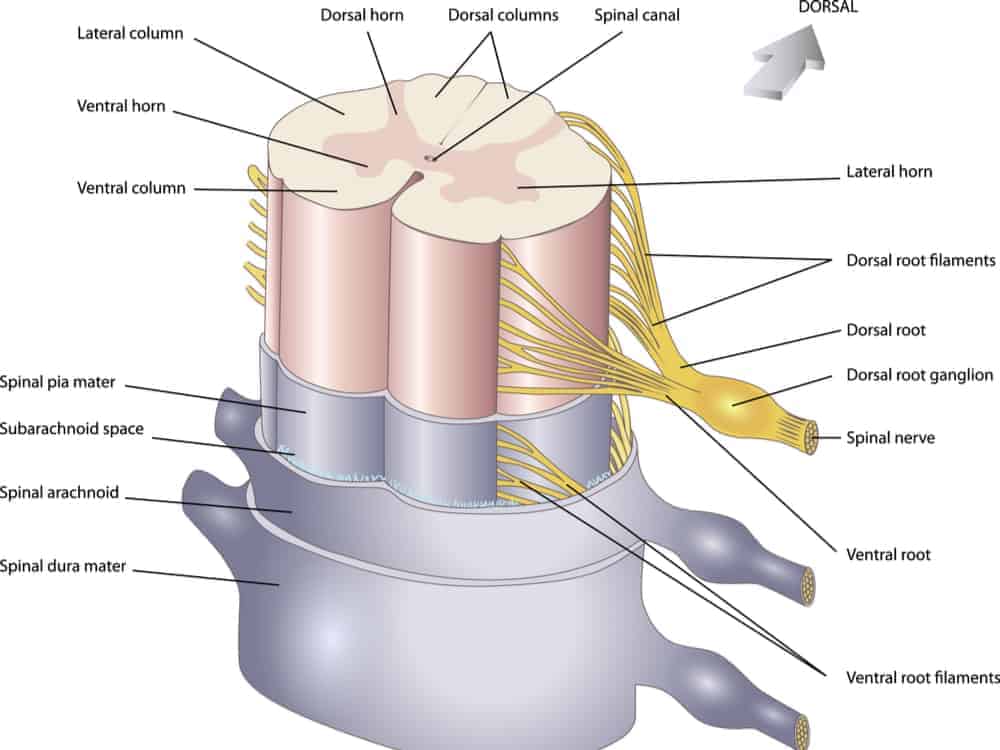

Sumsum Tulang Belakang Pengertian Letak Fungsi Struktur Dan Bagian Struktur Sumsum Tulang Belakang Medula Spinalis Manusia Lengkap

Sumsum Tulang Belakang Pengertian Letak Fungsi Struktur Dan Bagian Struktur Sumsum Tulang Belakang Medula Spinalis Manusia Lengkap

Struktur Dan Fungsi Sumsum Tulang Belakang Medula Spinalis Weschool Id

Struktur Dan Fungsi Sumsum Tulang Belakang Medula Spinalis Weschool Id